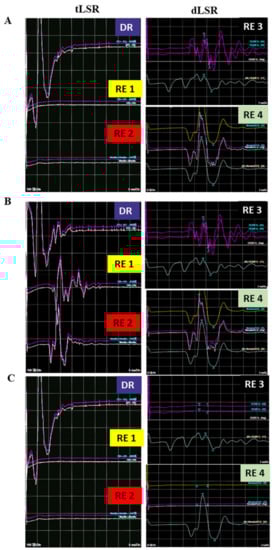

2.3.1. tLSR Measurement

2.3.2. dLSR Measurement